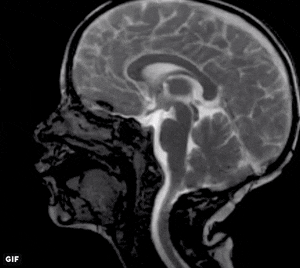

I mean it when I say it gets pumped around like the blood does. It pulses through the brain and and spinal cord at roughly the same rate as the heartbeats. We aren’t exactly sure why this happens or even how it happens, there is still a lot of debate around how this works, but we think it is due to the expansion and contraction of blood vessels as the heart is beating, which then puts pressure on the cord and brain and thus circulates the CSF. Below you can see an MRI video of the brain as the heart beats, this is definitely not a static system.